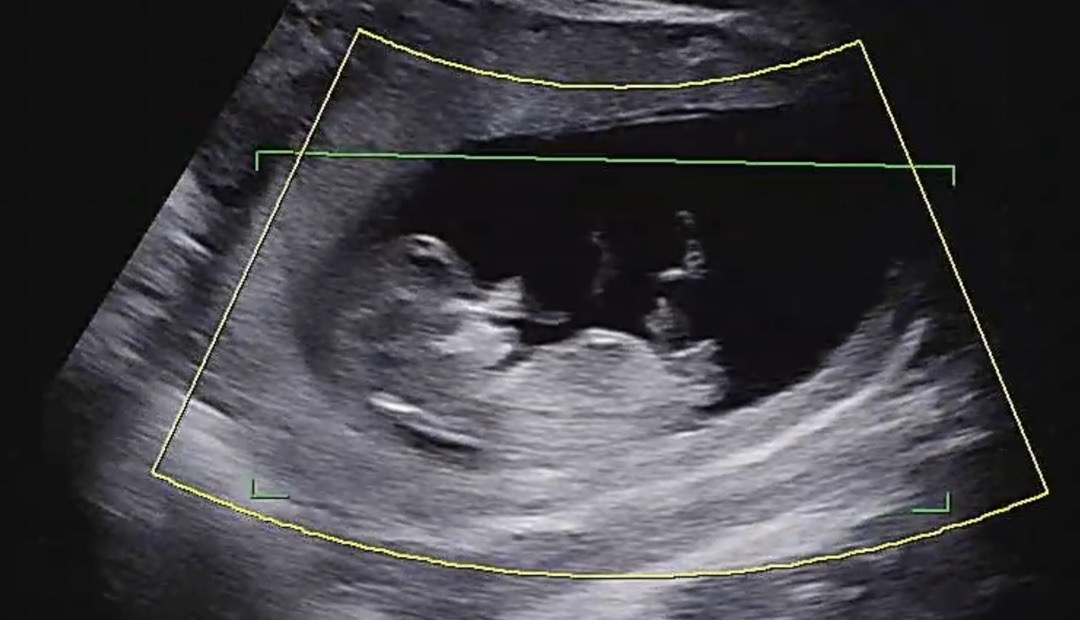

1차 기형아 검사하고 왔어용 (성별투표)

11주 2일차라 많이 이르긴한데, 각도법 한번만 봐주세용🫶🏻